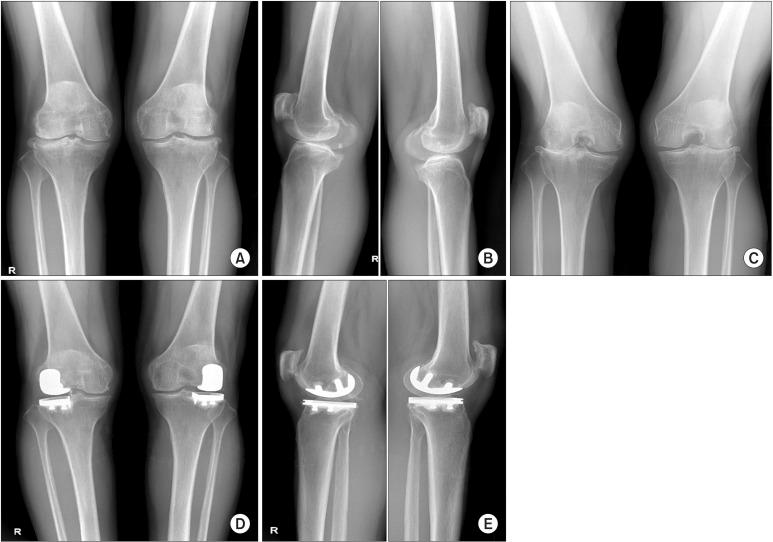

We investigated the clinical results and early complications after lateral unicompartmental knee arthroplasty (UKA) using the Zimmer unicompartmental high-flex knee (ZUK) prosthesis with a minimum follow-up of 2 years.

Twenty-seven patients (30 cases) who underwent lateral UKA with the ZUK prosthesis between January 2011 and February 2014 were selected for this study. The mean age of the patients was 63.3 years at the time of surgery, and the mean followup was 3 years and 2 months (range, 24 to 48 months). A retrospective investigation method was used to evaluate the clinical and radiographic results with use of the Knee Society (KS) clinical rating system and plain radiography.

The mean KS pain score was improved from 17.9 points (range, 10 to 30 points) preoperatively to 40.5 points (range, 30 to 45 points) at the final follow-up ( < 0.001). The mean KS knee score and function score significantly increased from 63.2 points (range, 48 to 70 points) and 68.6 points (range, 35 to 80 points), respectively, preoperatively to 86.0 points (range, 74 to 95 points) and 92.4 points (range, 60 to 100 points), respectively, at the final follow-up ( < 0.001). The mean range of motion of the knee was recovered from 127.1° (range, 110° to 135°) preoperatively to 131.6° (range, 120° to 135°) at the final follow-up. The mean tibiofemoral angle changed from 6.2° of valgus (range, 0.1° to 11.4° of valgus) preoperatively to 3.4°of valgus (range, 0.2° to 9.5° of valgus) at the final follow-up. The overall results classified based on the KS knee score were "excellent" in 21 cases and "good" in 8 cases. Revision total knee arthroplasty was required in one case because of consistent pain on the medial side of the knee after surgery.

The early clinical results of lateral UKA using the ZUK prosthesis were satisfactory for improvement of pain, knee score, function score, and recovery of knee motion. Therefore, the lateral UKA could be a useful method in the treatment of osteoarthritis in the lateral compartment of the knee. Long-term survivorship remains to be confirmed through ongoing follow-up.